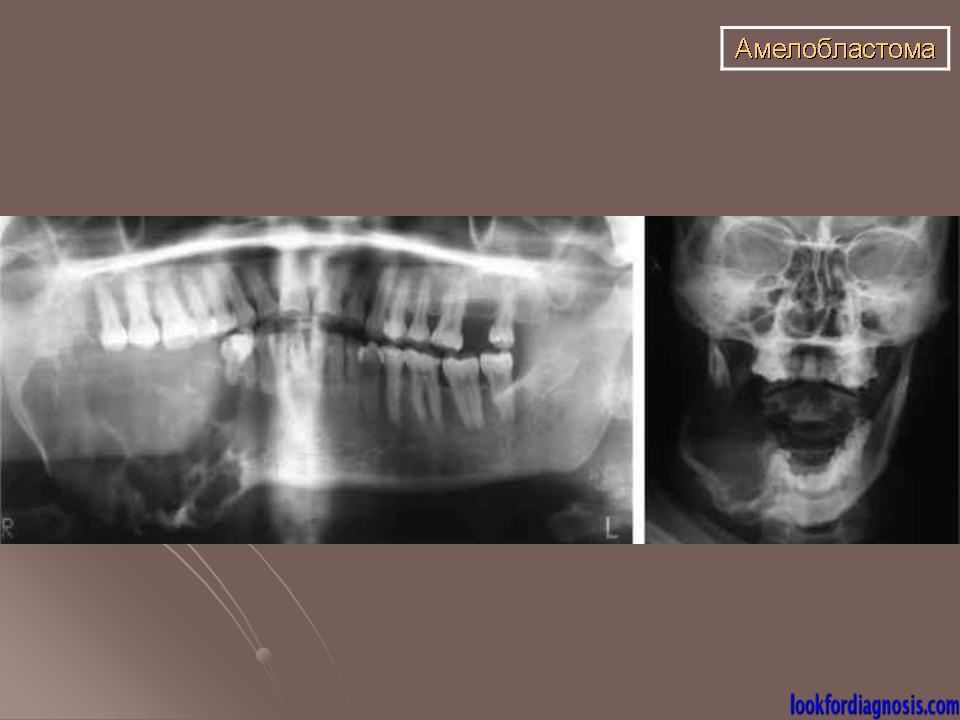

Амелобластома

ID: 18115 Ameloblastoma Dr Lawrence Josey - 10 Jun 2012 This case illustrates the plain films and CT features of an ameloblastoma.